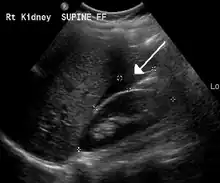

An ultrasound showing a gestational sac with fetal heart in the fallopian tube has a very high specificity of ectopic pregnancy. It involves a long, thin transducer, covered with the conducting gel and a plastic/latex sheath and inserted into the vagina.[32] Transvaginal ultrasonography has a sensitivity of at least 90% for ectopic pregnancy.[5] The diagnostic ultrasonographic finding in ectopic pregnancy is an adnexal mass that moves separately from the ovary. In around 60% of cases, it is an inhomogeneous or a noncystic adnexal mass sometimes known as the "blob sign". It is generally spherical, but a more tubular appearance may be seen in case of hematosalpinx. This sign has been estimated to have a sensitivity of 84% and specificity of 99% in diagnosing ectopic pregnancy.[5] In the study estimating these values, the blob sign had a positive predictive value of 96% and a negative predictive value of 95%.[5] The visualization of an empty extrauterine gestational sac is sometimes known as the "bagel sign", and is present in around 20% of cases.[5] In another 20% of cases, there is visualization of a gestational sac containing a yolk sac or an embryo.[5] Ectopic pregnancies where there is visualization of cardiac activity are sometimes termed "viable ectopic".[5]

Ultrasound image showing an ectopic pregnancy where a gestational sac and fetus has been formed